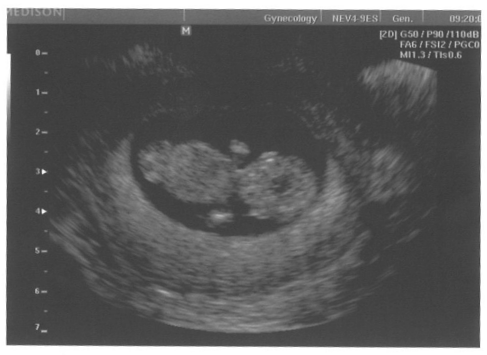

[392855] Paradni fotecka, ja uz se nemuzu dockat 5.12! a po kontrole do brna na screening :)